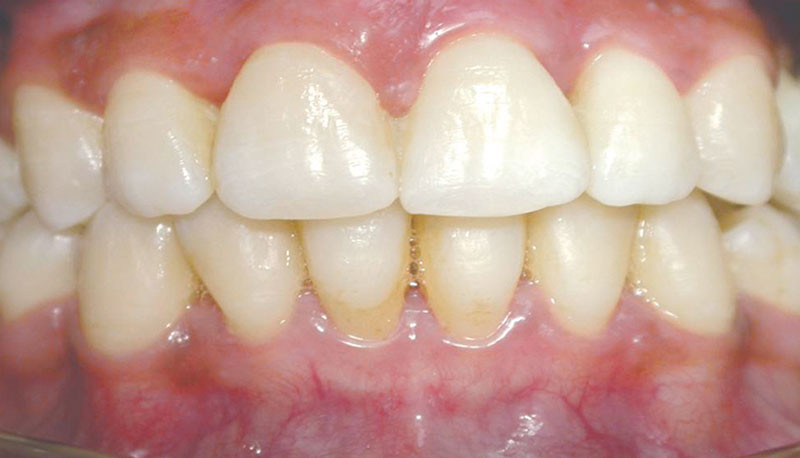

Une approche en équipe pour retrouver le sourire

La réhabilitation d’un sourire, qui plus est chez le patient parodontal, nécessite une approche pluridisciplinaire et un travail en équipe bien coordonné. En effet, le résultat esthétique dépend hautement de l’harmonie entre la gencive et la restauration prothétique. Dès lors, chaque étape du traitement a une importance majeure, depuis sa planification jusqu’à la réhabilitation prothétique en passant par la gestion des tissus mous et l’orthodontie.

L’objectif de cet exposé est de mettre en lumière la prise en charge pluridisciplinaire des réhabilitations esthétiques. Les challenges liés au patient parodontal seront mis en évidence à travers la description de plusieurs cas cliniques. L’accent sera également mis sur les nouvelles technologies et sur le choix des techniques et des biomatériaux.